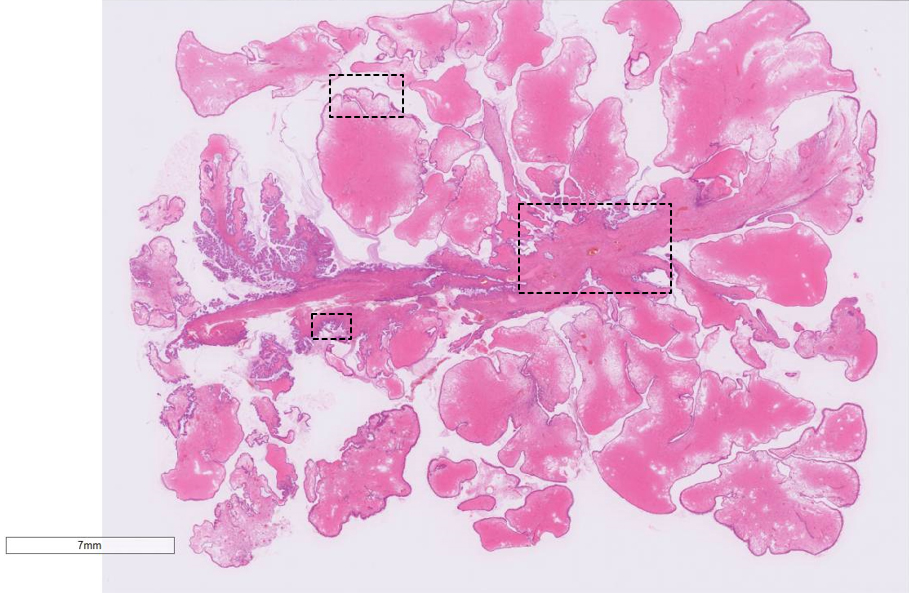

• HE ルーペ像